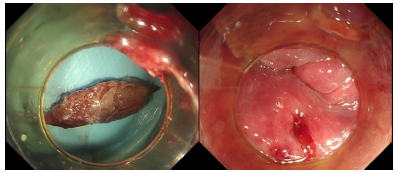

消化内科主治医师李浩然和微创中(第二手术区)心护士长刘骥为患者行内镜下食管内异物取出术。术中可见一枣核卡顿于食管入口处,周围黏膜充血水肿伴破溃。使用异物钳钳取枣核头端,拖入透明膜内与内镜共同退出。二次进镜,食管入口处黏膜可见血肿、破溃及少量渗血,并行内镜下空肠营养管置管术。

术中可见一枣核卡顿于食管入口处,周围黏膜充血水肿伴破溃

使用异物钳将枣核取出,食管入口处黏膜可见血肿、破溃及少量渗血。